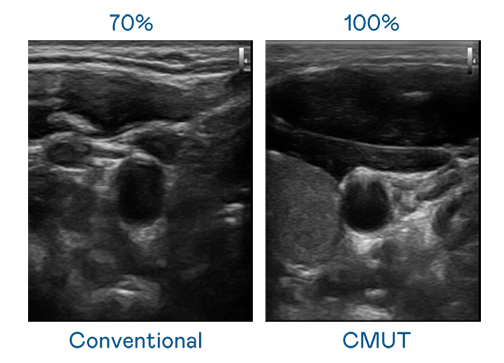

CMUT 技术是一种用电容式微机电元件来产生超音波讯号的技术。与传统 PZT 压电式技术相比,CMUT 频宽增加 30%,更宽频的超音波讯号让影像解析度大幅提升,是实现高影像品质医疗超音波扫描、促进精准医疗发展的关键技术。

超音波影像的解析度高低,首先取决于探头能发出的讯号频宽。EBpay CMUT 可提供高清晰的超音波讯号,提供高频宽、高灵敏度、影像纹理细节更高的超音波影像,协助医护人员缩短影像判读时间及利用精准的医疗影像进行诊断。